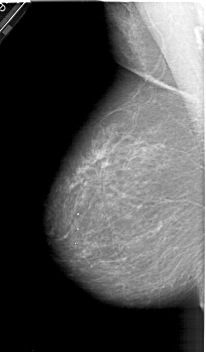

A_1321_1.LEFT_CC

LEFT_CC LINES 6796 PIXELS_PER_LINE 3571 BITS_PER_PIXEL 12 RESOLUTION 43.5 NON_OVERLAY